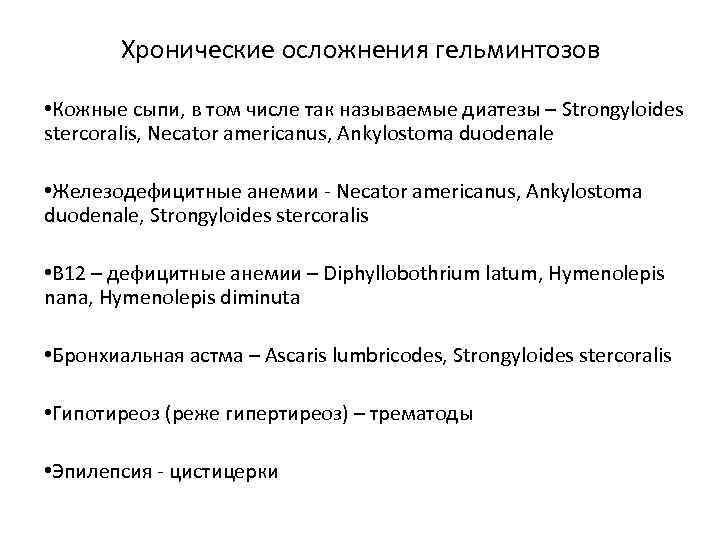

Хронические осложнения гельминтозов • Кожные сыпи, в том числе так называемые диатезы – Strongyloides stercoralis, Necator americanus, Ankylostoma duodenale • Железодефицитные анемии - Necator americanus, Ankylostoma duodenale, Strongyloides stercoralis • В 12 – дефицитные анемии – Diphyllobothrium latum, Hymenolepis nana, Hymenolepis diminuta • Бронхиальная астма – Ascaris lumbricodes, Strongyloides stercoralis • Гипотиреоз (реже гипертиреоз) – трематоды • Эпилепсия - цистицерки